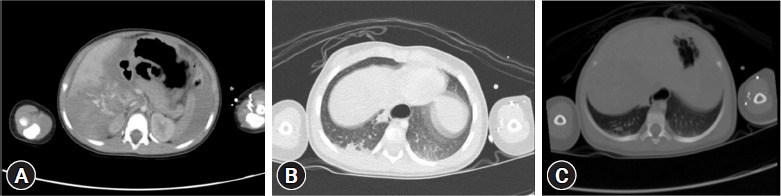

In Korea, helicopter emergency medical services (HEMS) with a physician on board were introduced in September 2011, funded by both central and regional governments. HEMS was integrated into the Korean emergency medical system to address the need for EMS in remote rural areas. The present report describes 16-month-old twins who fell from the fifth floor of an apartment building, located approximately 100 km from the nearest level I trauma center. Utilizing HEMS along with initial emergency management by an emergency physician, the patients were transported to the level I trauma center within the critical "golden hour." The children had sustained multiorgan injuries. Without intervention at the scene by an emergency physician, a fatal outcome was anticipated for both children. With the use of HEMS, one patient died, but the other survived with a good prognosis. The use of HEMS flights with an emergency physician on board may improve outcomes for pediatric patients with severe trauma in medically underserved rural areas.

Abstract Image